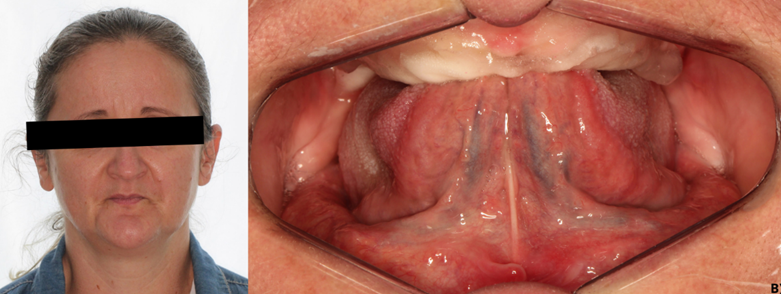

Paciente MZM, 48 anos, sexo feminino, com anemia em tratamento e sem mais complicações clínicas ou sistêmicas, compareceu à Faculdade São Leopoldo Mandic, em Campinas (SP), apresentando ausência de todos os elementos em arcada superior e inferior (Figura 1), se queixando sobre má adaptação de suas próteses removíveis e com intenção de iniciar sua reabilitação com implantes.